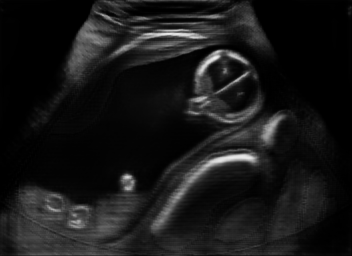

Real in-vivo images. 22 ultrasound sequences were collected using a GE Voluson E8 machine during standard fetal screening exams of 8 patients. Each sequence is several seconds long. We extracted all 4427 frames and resize them to , see Fig. 2 for some examples. The resulting image set was randomly split into training-validation-test sets by a 80-10-10% ratio.